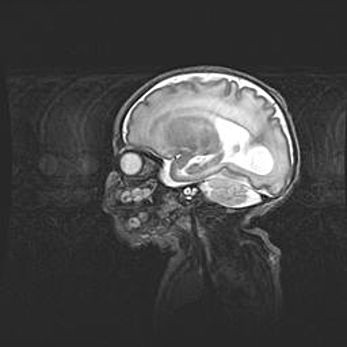

Неполная лизэнцефалия (пахигирия). Открытая гидроцефалия.

Возраст: 17 дней

Вес: 3110 г

Пол: мужской

Окружность головы: 33,5 см

Срок гестации: 35-36 недель

Лизэнцефалия—недоразвитие корковой пластинки и мозговых извилин в результате нарушения миграции нейронов коры. Поверхность мозговых полушарий гладкая. Микроскопически выявляется отсутствие нормальных слоев коры и скопление групп нейронов в подкорковом белом веществе.

Пахигирия—уменьшение числа вторичных извилин. В пораженном полушарии нервные клетки образуют толстый недифференцированный слой с неправильно расположенными нервными волокнами и группами гетеротопных клеток. Нервные клетки незрелые. Белое вещество истончено. При этом нередко аномально развит корково-спинномозговой путь.